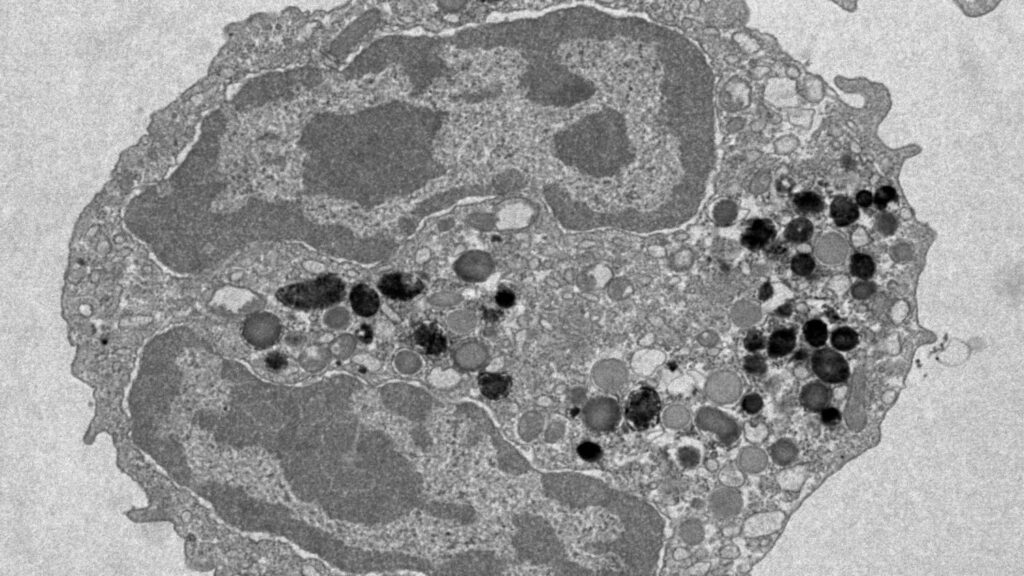

Blutstammzellen sind die Zellen, aus denen alle Blutzellen entstehen. Sie befinden sich im Knochenmark und sind für die Produktion neuer roter und weißer Blutkörperchen sowie Blutplättchen verantwortlich. Mit zunehmendem Alter sammeln sich in diesen Zellen genetische Veränderungen an. Manche Mutationen können das Risiko für Krankheiten wie Leukämie oder Herz-Kreislauf-Erkrankungen erhöhen.